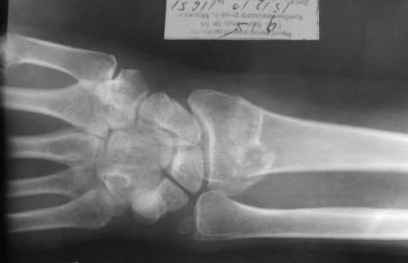

Уважаемые коллеги.Прошу обсудить случай лечения перелома дистального метаэпифиза лучевой кости. Ситуация скандальная и крайне неблагоприятная. Больная с патологической обстоятельностью мышления, склонностью к сутяжничеству, патологическими умозаключениями, не поддающимися коррекции (см. психиатрию, правда офиц. диагноза нет). В данном случае есть ряд ошибок с нашей стороны, прежде всего в отношении качества ведения документации (за что получил административное взыскание, по делом мне дураку). В остальном- придерживались в лечении подхода классический советской школы. Так как умную операцию…… сами знаете… 15.12- перелом луча в Москве. Там же репозиция, гипс. Дальнейшее лечение у нас в ЦРБ. 20.12.- вторичное смещение в гипсе21.12- под внутривенным наркозом- репозиция, гипсовая лонгета. Дальше начинается самое интересное. После репозиции больная заявила, что я (репозицию делал я) порвал ей все связки в суставе, посинел у нее 5 палец, якобы я за него тянул и т. д. На самом деле на 2 сутки после репозиции рука немного отекла и было незначительное сдавление гипсом, который был ослаблен. Дальнейшее лечение консервативное. Через 6 недель- гипс снят, назначено ЛФК. Пациентка крайне недовольна. Говорит, что на снимке у нее выступает кость, я ей сломал руку и.т.д. В общем началось. Пациентка прочитала в интернете наверное все, что есть по данной травме.По заключениями рентгенологов и консультанта из КДЦ областной больницы - стояние отломков допустимое. Объективно говоря- снижена высота лучевой кости, диастаз лучелоктевого сочленения, и не сросся шиловидный отросток. однако на РКТ при сравнении с другой стороной- разница незначительная. Дальше в одной из больниц нашей области и одной из больниц Москвы (вроде бы КГБ 53) врачи сказали, что репозиция сделана плохо. Нужна операция (восстановить длину лучевой кости), даже один из них предложил РЕДРЕССАЦИЮ (хи-хи) с наложением аппарата Илизарова. Что это для данной больной- радость неописанная. (см. описание психического статуса). Ничем другим, кроме зарабатывания дешевого авторитета объяснить данный факт не могу.Кстати, у больной еще нейропатия локтевого нерва.Для разрешения конфликта больная направлена на консультацию в ЦИТО на 03.03.11.

Теперь вопросы: 1.Прошу объективно оценить качество нашей репозиции на момент 21.12. (неужели так плохо?). Что на снимках при снятии гипса- сам вижу. 2. сравнить снимки РКТ (с двух сторон)- так ли велико укорочение лучевой кости и лучелоктевой диастаз. 3. Ваши мнения, в отношении целесообразности оперативного лечения учитывая ВСЕ вышеизложенное. 4. На всякий случай для суда- мог ли я тракцией в 2- 3 кг за 1 и 2 пальцы под внутривенным наркозом неправильно вколотить отломки и травмировать локтевой нерв. Кстати, в США если врач пациенту говорит, что его плохо лечили- то этого врача лишают лицензии. У нас наооборот- обгадить другого милое дело. И это процветает. От себя же могу сказать, что никто в нашем отделении так не поступает. Коллеги, будьте осторожны в своих высказываниях. От осложнений и ошибок никто не застрахован. А в данном случае многое будет зависеть от заключения консультантов поликлиники ЦИТО, куда больная направлена областным травматологом на 03.03 для решения вопроса о дальнейшей тактики лечения. С уважением ко всему травматологическому сообществу Дедок Михаил.

1. РЕПОЗИЦИЯ сделана качественно(ОСНОВНЫЕ 2 УГЛА ВЫСТАВЛЕНЫ ПРАВИЛЬНО ) , но перелом нестабильный и склонен к втор смещению . Поэтому мы стараемся все переломы со смещением фиксировать 3-МЯ спицами по GRIN методике .

2. По сравнению и без ! втор смещение незначительное.НЕТ НИКАКОЙ ,,локтевой косорукости,,маделунгов . но имеется смещение совести у врачей КГБ 35--НЕТ ЗДОРОВЫХ, есть только недообследованные ! Этому смещению аппарат внешней фиксации не поможет .Психопаткам в менопаузе да весной только этого и надо чуть толкнули и поехало .

1. Репозиция от 21.12.10 была выполнена лучше, чем первичная.

2. Укорочение лучевой кости с изменениями дистального лучелоктевого сустава требует оперативного лечения

Заключение: Консолидированный в неправильном положении перелом дистального метафиза левой лучевой кости. Ротационная контрактура левого предплечья. Рекомендовано- разработка, консультация через 2 месяца.